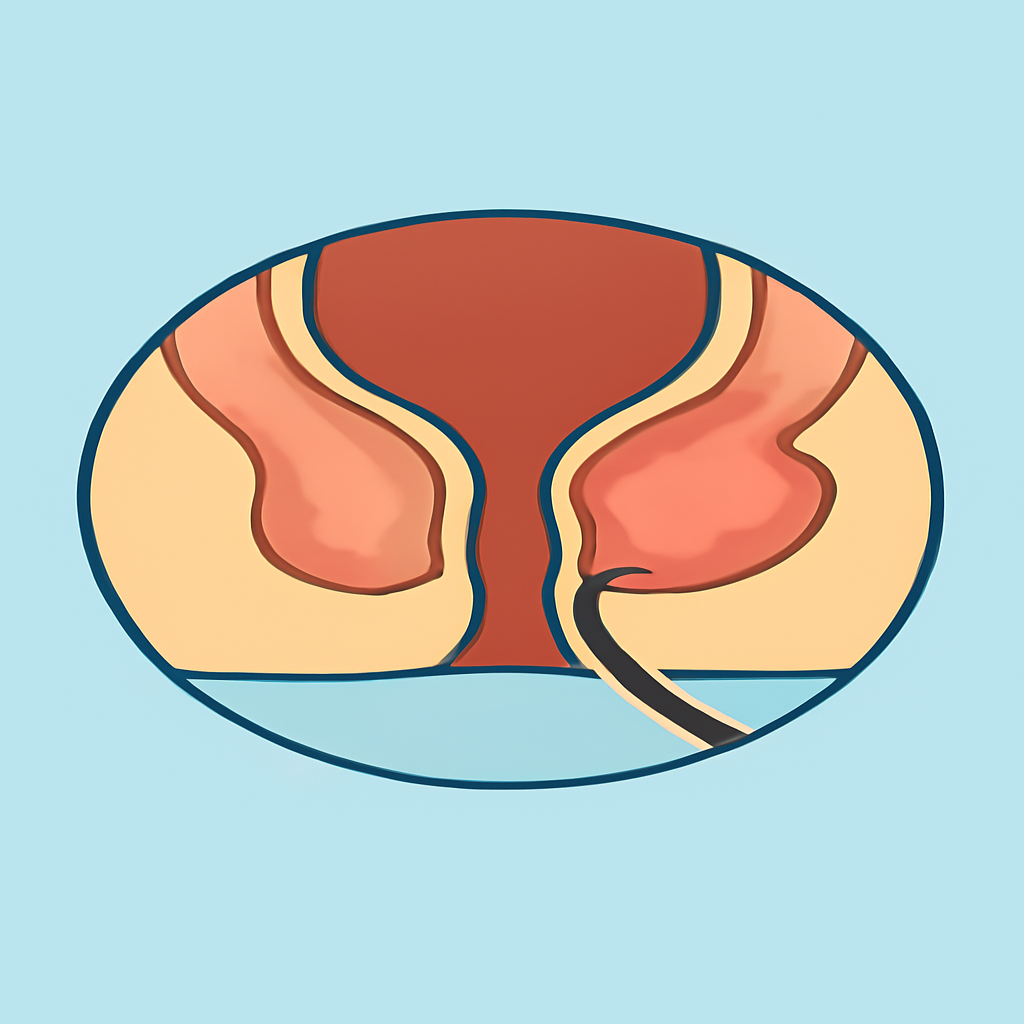

# Anal and Digestive